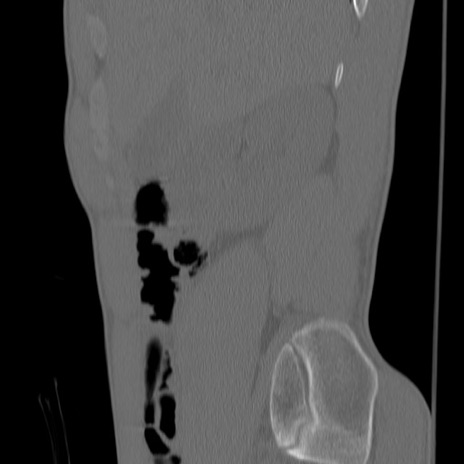

症例3 腰椎CT(矢状断像)

【症例】30歳代男性

【主訴】腰痛

【現病歴】本日旅行先で観光中に、友人と衝突し転倒し受傷。

【身体所見】麻痺なし、右下腿内側前面外側、左下腿内側に知覚鈍麻・しびれ

腰椎CT

冠状断像